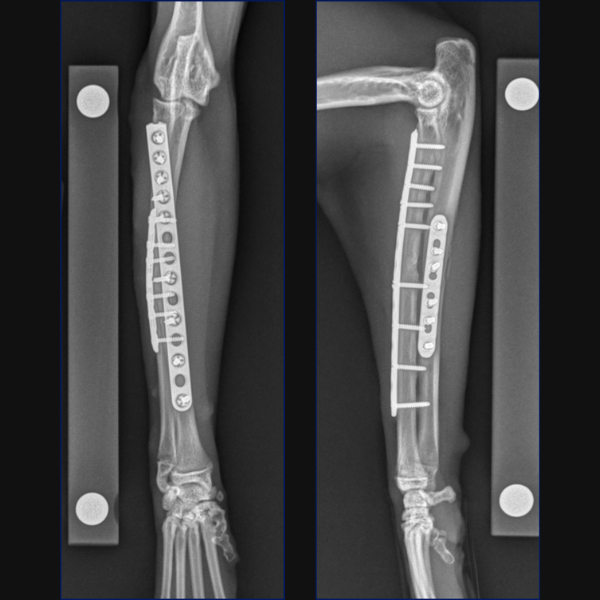

Separate minimally invasive approaches were made for the radial and ulnar fractures to facilitate placement of a 10-hole 1.5/2.0 LCP cranially on the radius with 3 screws proximally and 3 distally. A 7-hole 1.5/2.0 LCP was then placed laterally on the ulna through proximal and distal stab incisions. Lastly, the ulnar styloid fracture was stabilized minimally invasively through a stab incision using a 1.2mm K-wire.